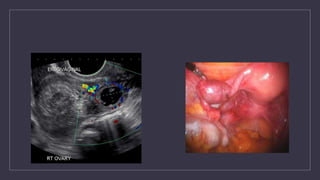

• A 27 year nulliparous lady (marital life 5 yrs) had come for infertility treatment

• Her usg shows this picture

• Comment on this

• Any other tests for the same..?

30 yrs , primary infertility for 3yrs , undergone ovulation induction and now has come with pain

abdomen and vomiting and her USG showed this picture

Diagnosis

Classification

Management and prevention